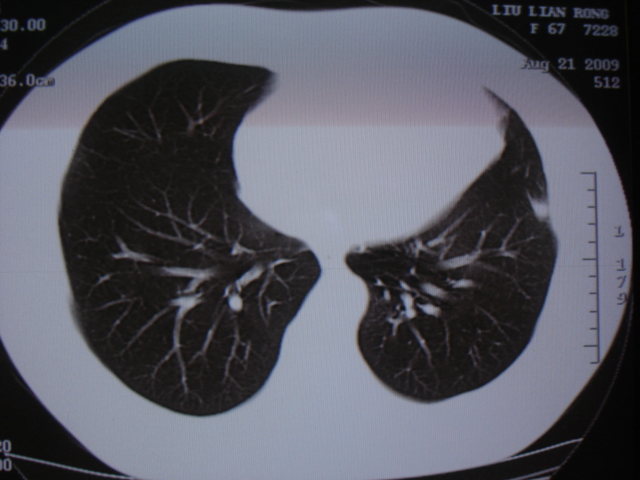

第一次ct2009.6.4

第二次ct2009.6.7 住院后ect未见异常,查痰(阴性)大量抗菌素抗炎一个月后病灶明显变小,7月5号出院后回家后口服抗菌素45天

第三次ct2009.8.21